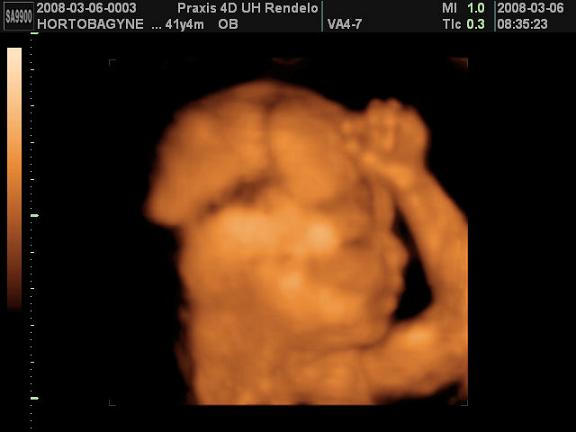

Sziasztok!

Most jöttünk meg a Praxisból, nagyon jó volt :lol: A doki mindjárt mondta hogy nem valami jól fekszik baba a látvány szempontjából de azért csinált pár képet profilból. Nem sokat mocorgott de azt többször láttuk hogy éppen ásít :D Anna jól viselte, úgy helyezkedtek apjával hogy ne azt lássa, hogy velem mit csinálnak, hanem a monitort. Érdeklődve nézegette a babát, bár a tekintetén látszott hogy kicsit furcsállja a látványt :lol: . A doki megerősítette:150% hogy fiú, bár nem tudta jól megmutatni mert Öcsike rajta ült a fenekén, de azt mondta szakember számára biztosan látszik a herezacskó. Persze a genetika eredménye alapján már tudtuk, de a férjem mégis kicsit kételkedett mert ezt nem adták ott írásba, csak szóban mondták... :wink:

És a lényeg persze hogy a vizsgálat alapján mindent rendben talált :D Teszek fel képet, remélem kivehető nagyjából az arca, és a keze :D